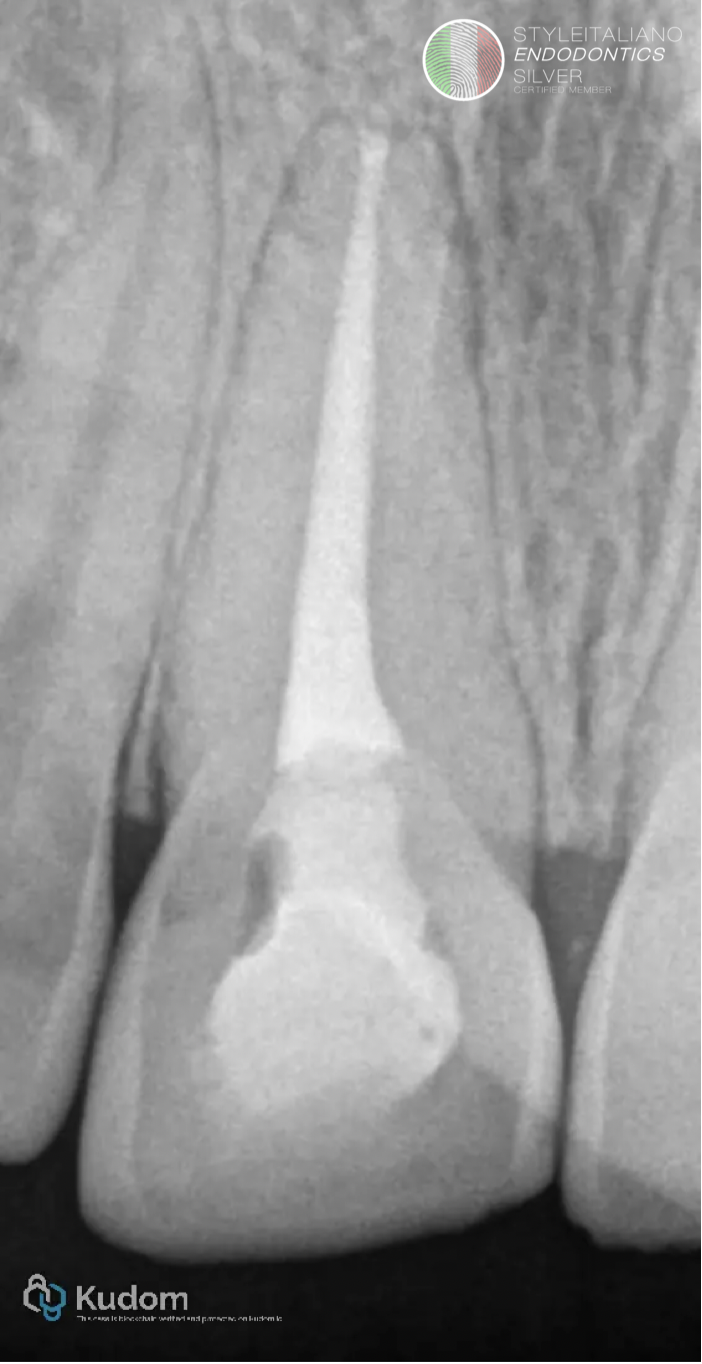

Fig. 10

Post-op X-Ray with final restoration.